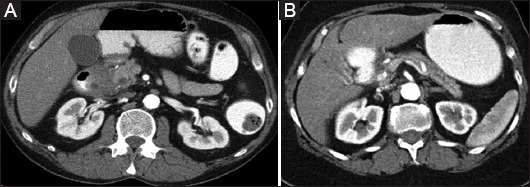

Background: Paraduodenal pancreatitis (PP) is an inflammation involving the groove zone, delimited by the duodenum lumen, bile duct, and the head of the pancreas. This area may also be involved during acute pancreatitis (AP). The differential diagnosis is clinically relevant, since PP generally persists, whereas AP resolves. Hence, we compared a cohort of patients with PP and AP involving the groove area.

Results: The study population consisted of 37 patients (32 men, age 56.9±9.1 years), 25 with a diagnosis of PP (23 men, mean age 54.9±8.5 years), and 12 (9 men, mean age 61.2±9.2 years) with AP involving the groove. All 25 patients with PP and 4 (33.3%) with AP reported a history of alcohol abuse, 23 patients (92%) with PP, and 3 (25%) with AP had a history of smoking. On imaging, PP patients presented a significantly thicker duodenal wall compared to the AP group (P=0.010). Chronic pancreatitis in the body/tail and exocrine insufficiency was prevalent in PP (P<0.001 and P=0.02). The medial displacement of the gastroduodenal artery was more frequent in the PP group (P=0.011).

Conclusion: PP has a different clinical and imaging profile compared to AP involving the groove area.